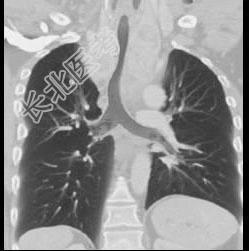

- 单项选择题男,67岁, 呼吸困难半年余,请结合影像学检查, 选出最可能的诊断 ( )

A、胸骨后甲状腺肿

B、淋巴瘤

C、间皮囊肿

D、纵隔畸胎瘤

E、胸腺瘤